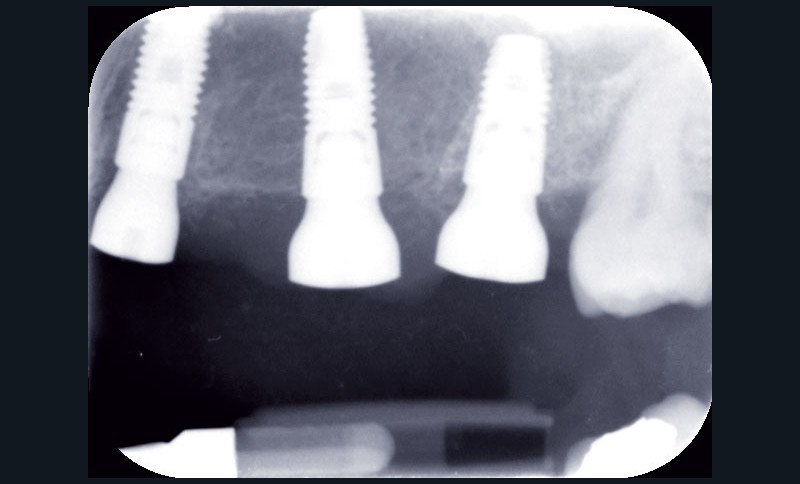

Au maxillaire, 3 implants Astra Tech Implant EV (Dentsply) sont posés en un temps chirurgical. Une empreinte pick-up sera réalisée après 4 mois de cicatrisation.

Une fois les transferts pick-up EV® transvissés, le porte-empreinte Tray, fenestré en regard des transferts, est chargé de matériau monophase Impregum™ Penta™ Soft (3M ESPE). Du matériau est déposé autour des transferts à l’aide d’une seringue. Après dévissage des transferts, ces derniers sont emportés dans l’empreinte et les analogues d’implants sont transvissés.

Une fois les transferts pick-up EV® transvissés, le porte-empreinte Tray, fenestré en regard des transferts, est chargé de matériau monophase Impregum™ Penta™ Soft (3M ESPE). Du matériau est déposé autour des transferts à l’aide d’une seringue. Après dévissage des transferts, ces derniers sont emportés dans l’empreinte et les analogues d’implants sont transvissés.

Une fois les transferts pick-up EV® transvissés, le porte-empreinte Tray, fenestré en regard des transferts, est chargé de matériau monophase Impregum™ Penta™ Soft (3M ESPE). Du matériau est déposé autour des transferts à l’aide d’une seringue. Après dévissage des transferts, ces derniers sont emportés dans l’empreinte et les analogues d’implants sont transvissés.

Une fois les transferts pick-up EV® transvissés, le porte-empreinte Tray, fenestré en regard des transferts, est chargé de matériau monophase Impregum™ Penta™ Soft (3M ESPE). Du matériau est déposé autour des transferts à l’aide d’une seringue. Après dévissage des transferts, ces derniers sont emportés dans l’empreinte et les analogues d’implants sont transvissés.

Une fois les transferts pick-up EV® transvissés, le porte-empreinte Tray, fenestré en regard des transferts, est chargé de matériau monophase Impregum™ Penta™ Soft (3M ESPE). Du matériau est déposé autour des transferts à l’aide d’une seringue. Après dévissage des transferts, ces derniers sont emportés dans l’empreinte et les analogues d’implants sont transvissés.